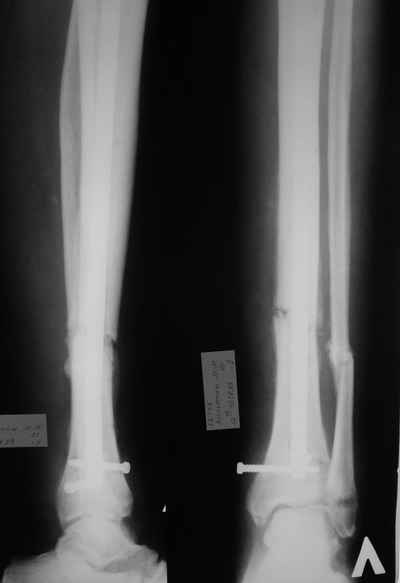

У пациента 55 лет после открытого перелома костей голени остро развилось глубокое нагноение

верхней трети голени.

При вскрытии 2 дня назад около 80 мл сливкообразного гноя. Спица удалена (видимо она и была

причиной инфицирования), винты нестабильны - также удалены. Гвоздь оставили на месте

(пока). Дном гнойной раны явлется кость, зонд доходит до гвоздя. в настоящее вроем рана

дренируется выпускниками, количество отделяемого уменьшается....

Открытый перелом- пхо+стержневой аппарат-штифтование. Через 4 месяца отек, температура 39….